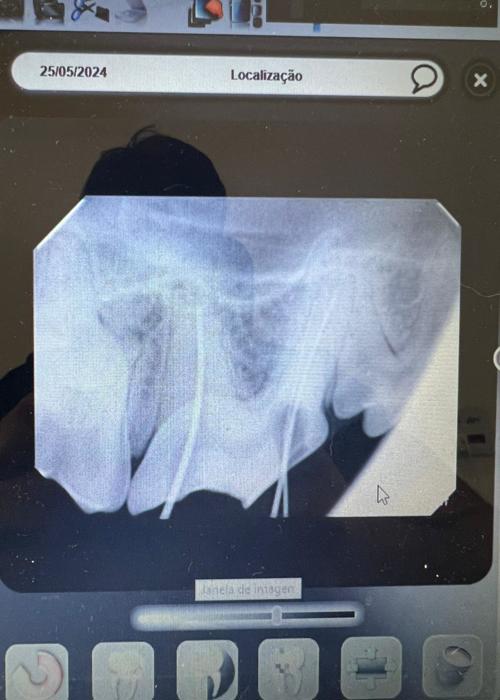

Realizamos tratamentos odontológicos completos, atuando desde a prevenção até procedimentos clínicos e cirúrgicos.

Identificamos precocemente problemas bucais, orientando tutores e evitando complicações que podem afetar outros órgãos do pet.

Contamos com estrutura moderna e equipada, garantindo atendimentos com mais segurança, precisão e conforto aos pets.